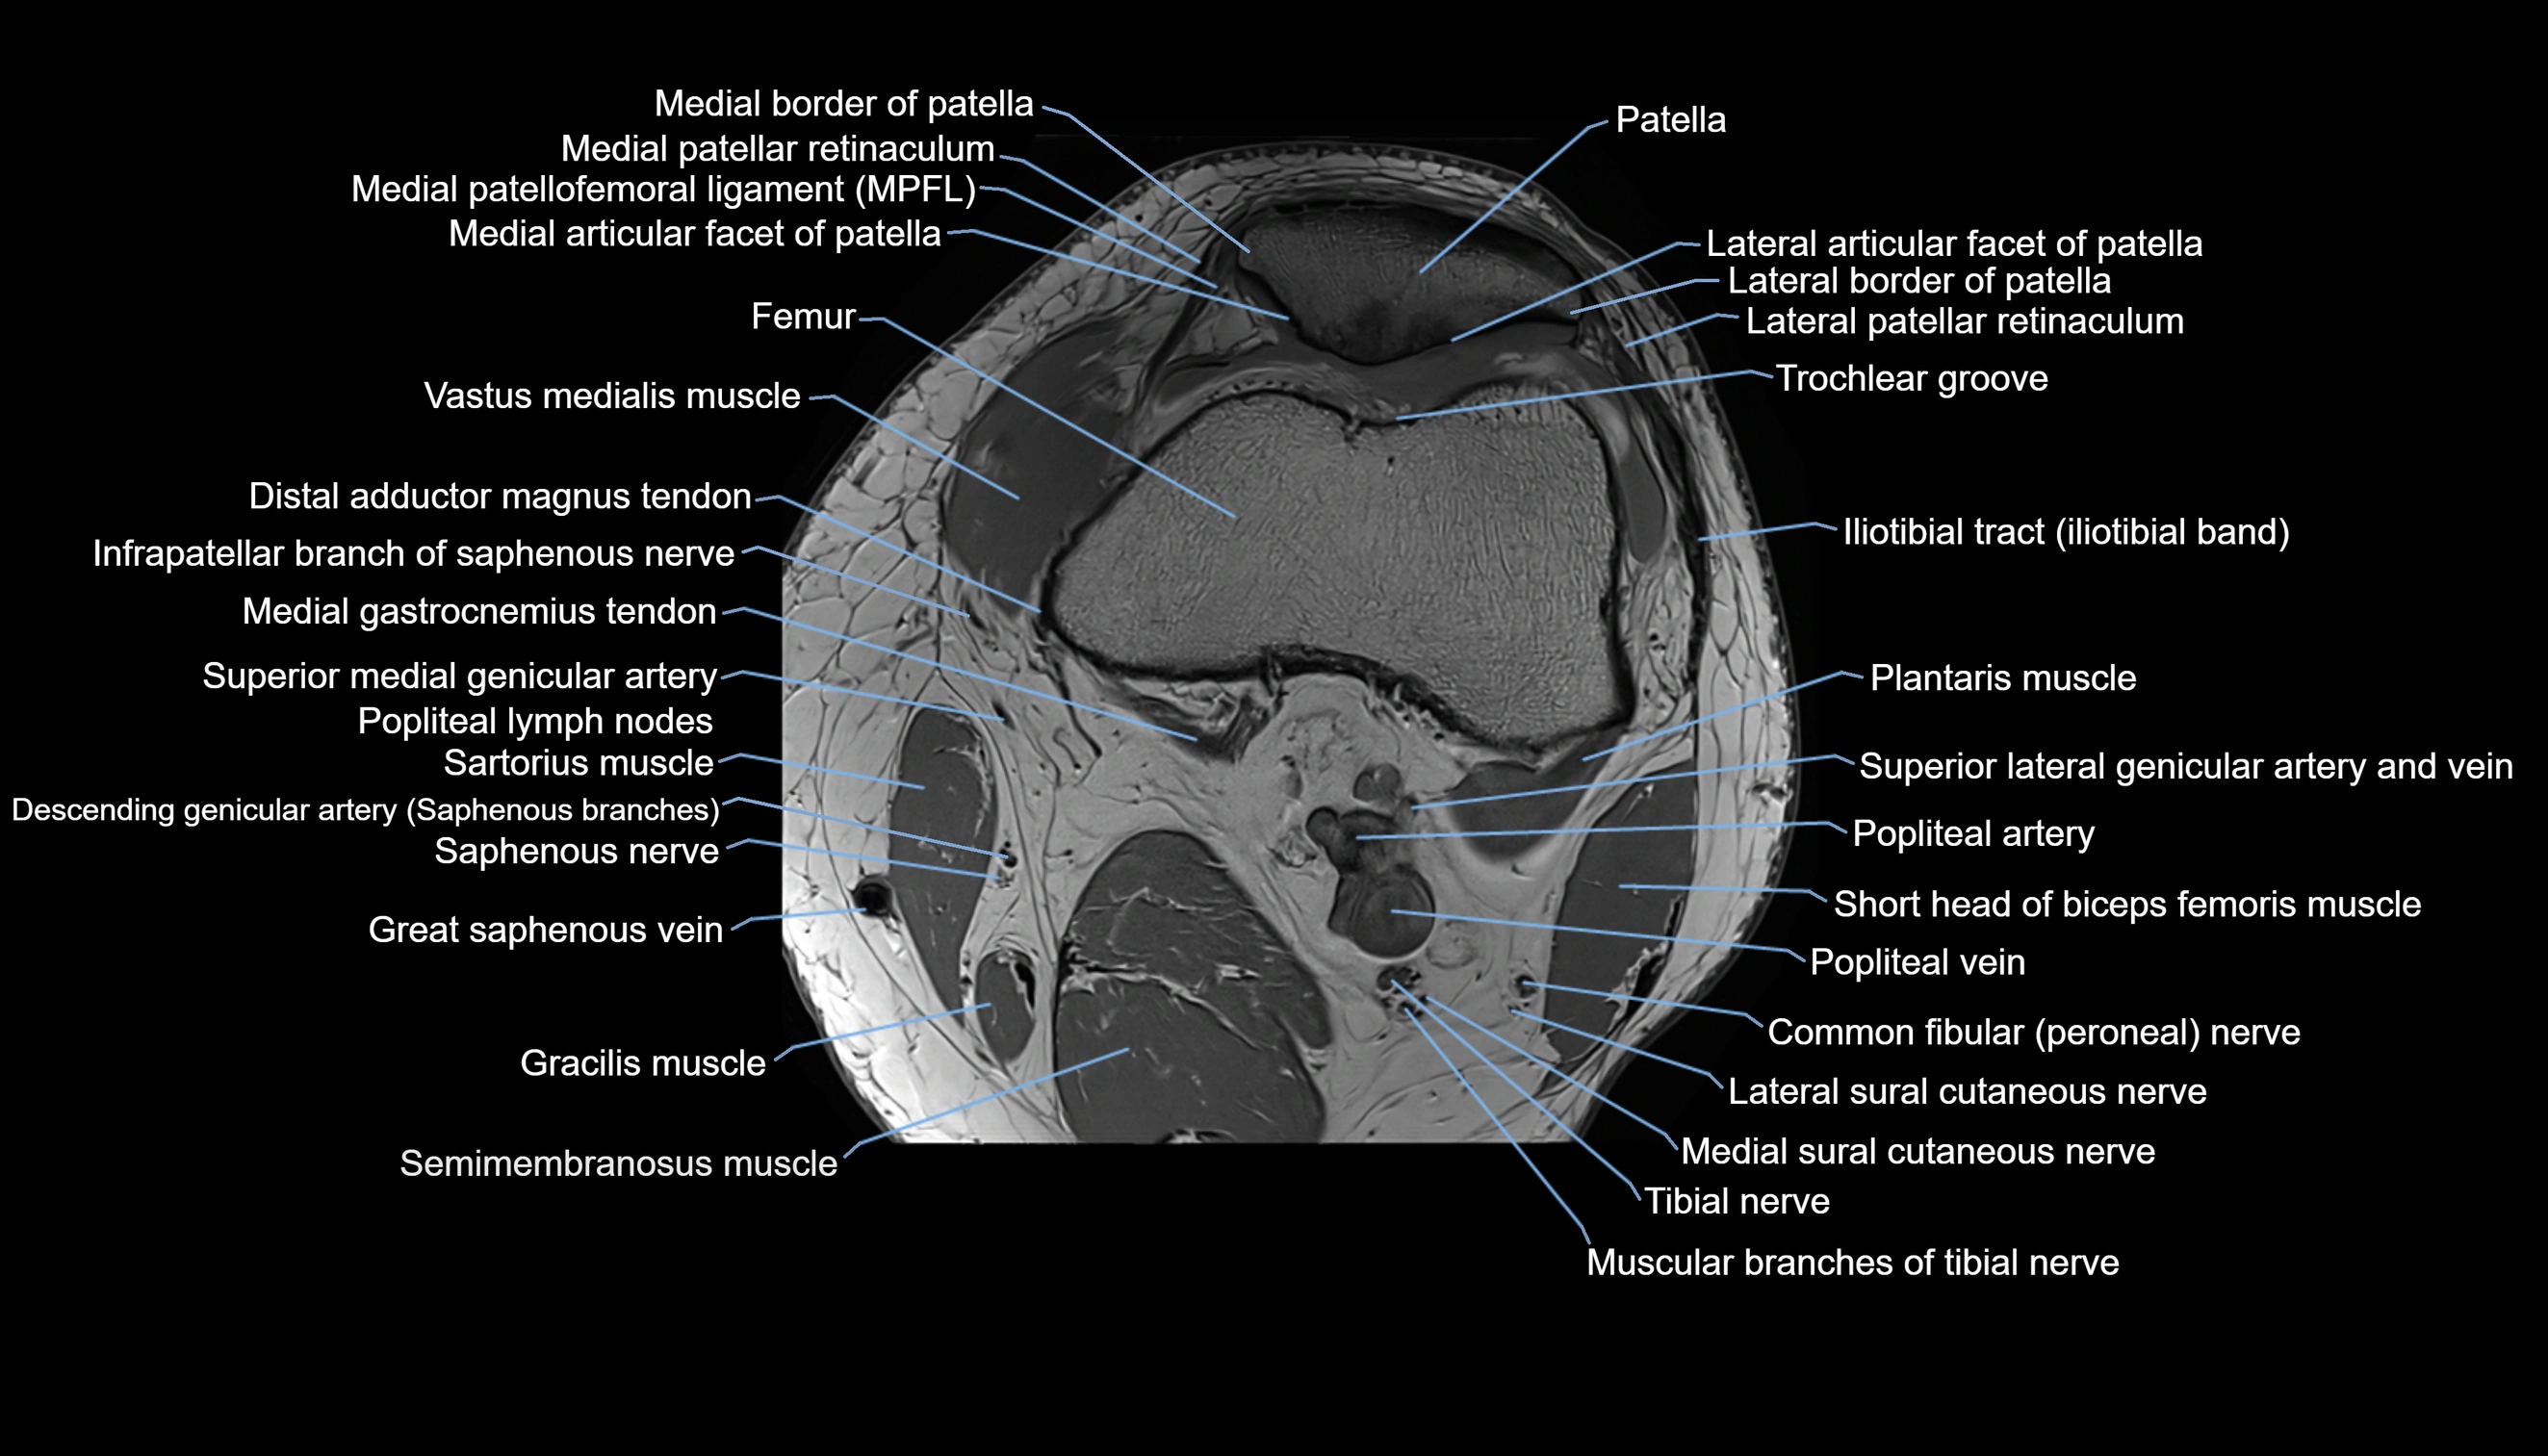

- Lateral articular facet of patella

- Lateral border of patella

- Lateral patellar retinaculum

- Lateral patellofemoral ligament

- Medial articular facet of patella

- Medial border of patella

- Medial patellar retinaculum

- Medial patellofemoral ligament

- Patella

- Popliteal artery

- Popliteal vein

- Lateral sural cutaneous nerve

- Medial sural cutaneous nerve

- Muscular branches of tibial nerve

- Plantaris muscle

- Popliteal lymph nodes

- Sartorius muscle

- Semimembranosus muscle

- Trochlear groove